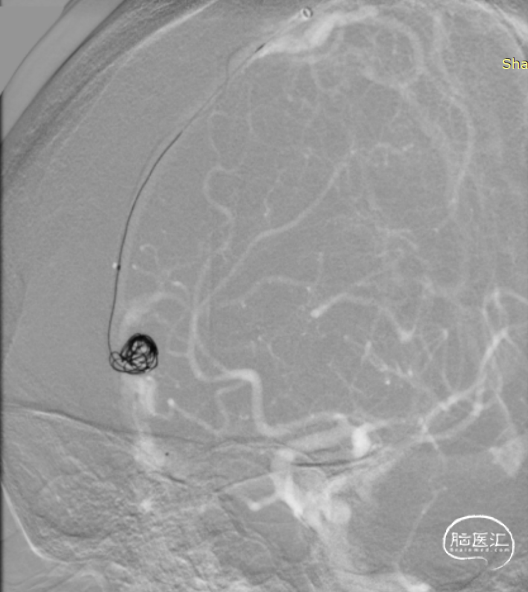

Echelon微导管经DCwire™微导丝,经过近端扭控,远端克服刁钻“回转弯”后引导微导管顺利进入近端静脉球。后马拉松微导管到达近动脉瘘口。

DCwire™微导丝配合Echelon微导管、通过优秀的扭控到位性及输送性,为微导管顺利到位提供保障。通过Echelon微导管首先稳定栓塞近端静脉球。

近端静脉球弹簧圈致密栓塞后,经马拉松微导管注入Onyx18。